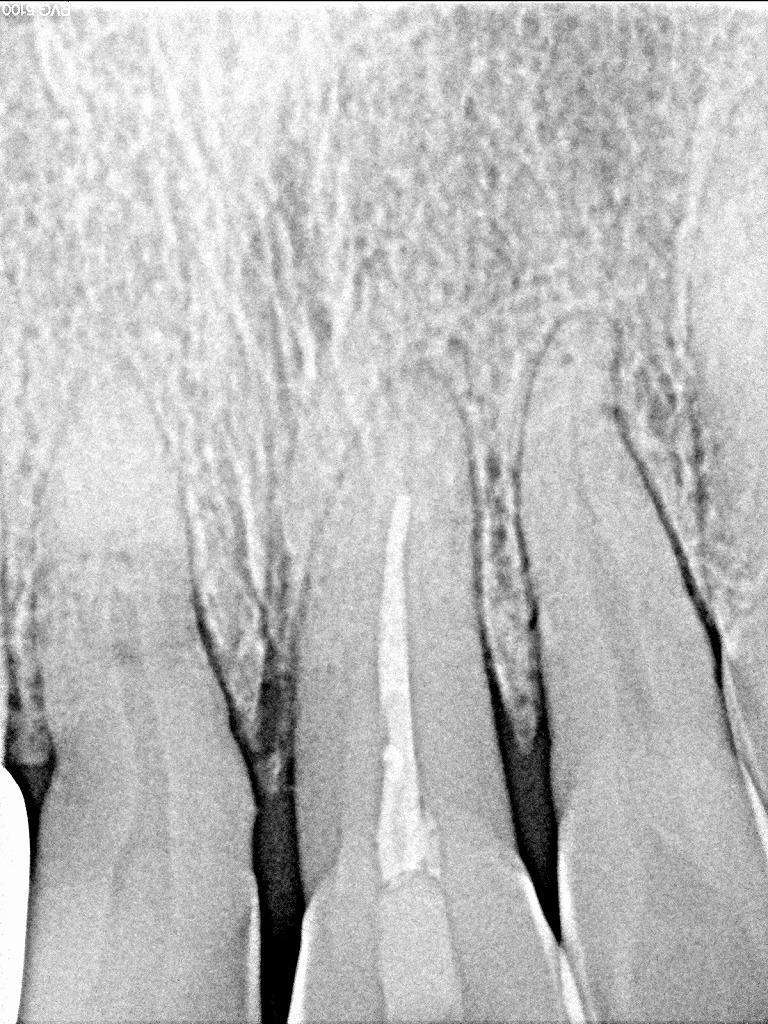

デンタルレントゲンになります

このレントゲンでは分かりにくいのですが、、、

右上1番部が骨内にて根が破折しています

根尖部で折れていました

根尖部にて破折していました